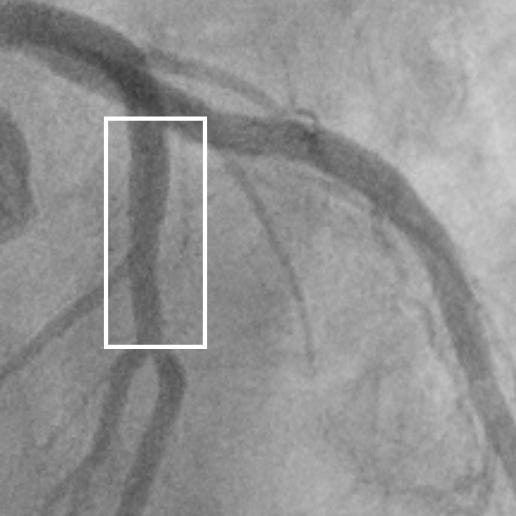

For decades, the ICA (commonly termed “cardiac catheterization or cath”) was considered the “gold standard” for the assessment of the arteries to the heart (the coronary arteries.) This invasive test involves inserting a tube (catheter) into either an artery in the wrist or groin2, threading the catheter up the artery to the aorta, and injecting contrast dye directly into the coronary arteries.

The x-ray movie images (angiogram) obtained then show the dye within the lumen of the arteries. If the column of dye is impinged upon an obstruction is diagnosed. However, early plaque in the arteries doesn’t necessarily stick into the lumen and typically resides in the wall, hidden from these “lumenograms.”

Below are the freeze-frame images of the left coronary artery invasive angiogram from a man we shall call Jerry who underwent catheterization in his 40s for atypical chest pain. He was told he had normal arteries, that they were “clean”.